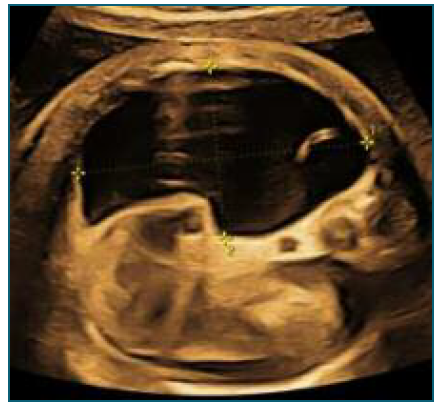

At 32 weeks (Figure 1), the fetus was found to have imaging findings consistent with fetal hydrops (bilateral pleural effusion and ascites), showing a sudden deterioration compared to the ultrasound performed at 28 weeks. Flowmetry was normal, but considering the worsening, a multidisciplinary meeting opted for hospitalization with induction of lung maturation and placement of pleuro-amniotic shunt.